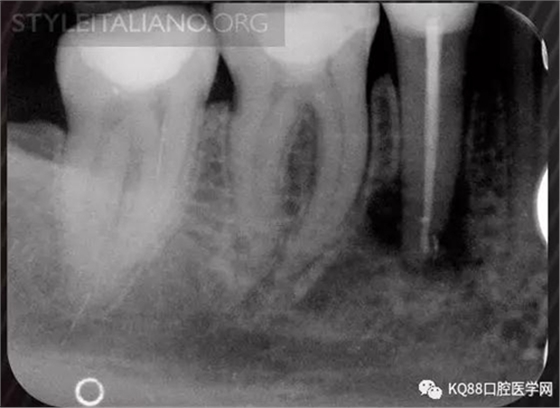

Case 1: In this patient, persistent pain was present after endodontic treatment of a vital tooth. The periapical x-ray showed an inadequate shaping of the distal root canal, regarding both the working length and the apical taper.

Img. 2 - Retreatment of distal canal was performed using ProTaper retreatment files. Working length was assessed electronically. Canal was shaped with a Reciproc R40, thoroughly irrigated with US activation, filled with corresponding Guttafusion obturator. Pain disappeared completely some days after retreatment. In all likelihood, incomplete preparation allowed residual pulp tissue to remain in the root canal, acting as an irritant.